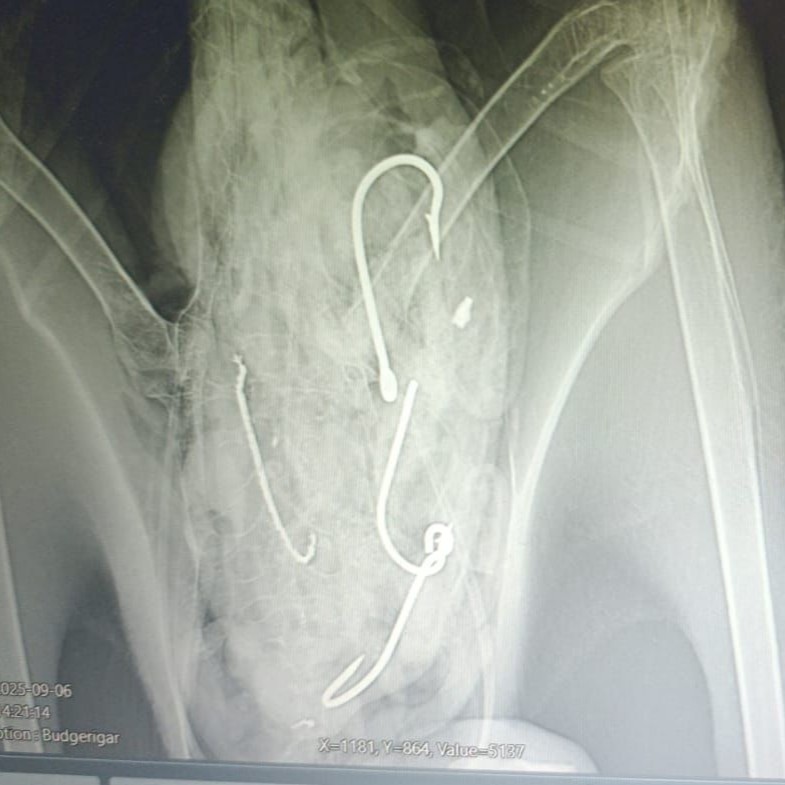

Four fishing hooks and fishing line are visible in this X-ray of a Salvin’s Albatross, photograph by Ruben Aleman, Fundación Juvimar

“The juvenile Salvin's Albatross was found by Juan Alberto Infante, a fisherman from Anconcito, Ecuador, who recognized that the bird was unwell and contacted local authorities. The albatross was under wildlife rehabilitation care in Puerto López after the ingested hooks and fishing line were successfully removed by Ruben Aleman, a local veterinarian with Fundación Juvimar. After careful evaluation, it was released in late October on a nearby beach in Manabí province. Thanks to the timely report from an artisanal fisher, we were able to rescue this Salvin's Albatross that had been grounded for several days in the port of Anconcito, said Giovanny Suárez Espín, Ecuador Seabird Bycatch Coordinator for American Bird Conservancy (ABC). Through coordination with Ecuador's Ministry of the Environment's local representative (REMACOPSE) and a specialized veterinarian, we successfully removed four fishing hooks from the bird, including one that caused injuries to its esophagus. The type and size of the hooks suggest they came from the artisanal mahi-mahi [Coryphaena hippurus] fishery, which poses a risk to albatrosses.